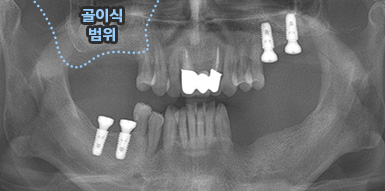

골이식 임플란트

치조골 이식술이란?

치주염 등으로 치조골(잇몸뼈)의 양이 부족한 경우

치조골 이식술을 통하여 충분한 뼈의 양을 확보한 후

임플란트를 식립합니다.

뼈의 밀도가 치밀하고 단단하며, 양이 충분할수록 임플란트의 성공률이 높아집니다.

청담네오플란트는 풍부한 경험의 의료진이 치조골 이식술을 통해 치조골을 적절한 양과

밀도로 재생시킨 후 임플란트를 식립합니다. 뼈의 흡수가 심하지 않아 적은 양의

치조골 이식을 하는 경우 임플란트 식립을 동시에 진행할 수 있지만, 뼈의 흡수가

심하여 많은 양의 치조골 이식이 필요한 경우 치조골 이식술을 먼저 진행한 후,

치조골이 재생되면 임플란트를 식립하여 보다 정밀하고 안전한 시술 결과를 얻을 수 있습니다.